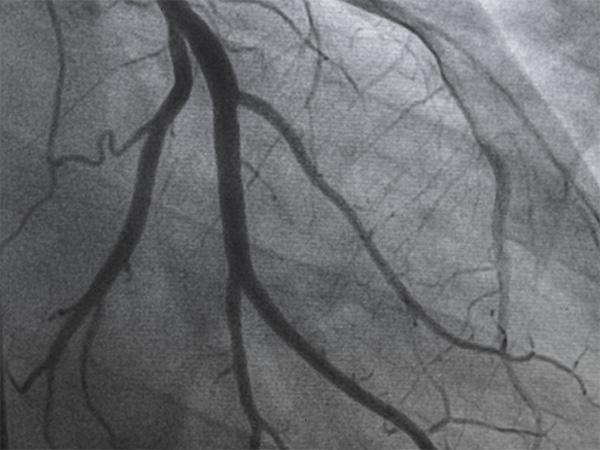

Mintz advised Royal Philips on its agreement to acquire SpectraWAVE, enhancing Philips’ intravascular imaging and AI-driven physiology solutions for coronary artery disease treatment.